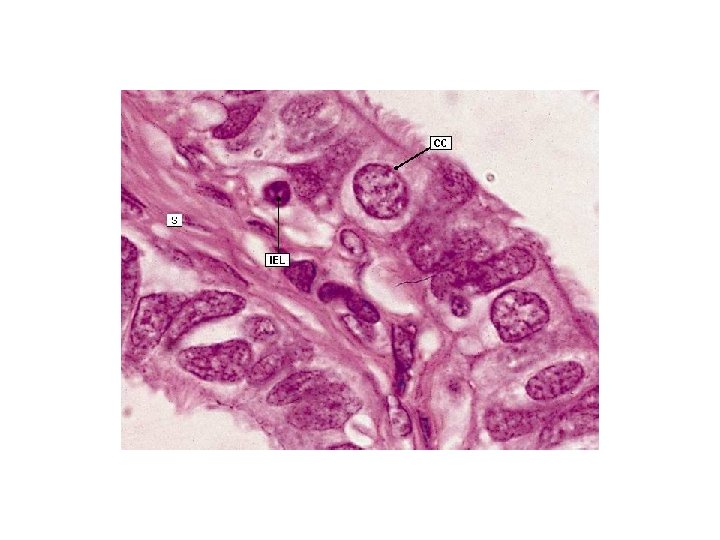

Oviduct àUterine tube is a muscular tube, 12 cm long àIt is the site of fertilization àUpper end opens into peritoneal cavity near ovary àLower end passes through the uterus wall àOviduct has 4 segments îintramural part in uterine wall îisthmus is adjacent to uterine wall îampulla is dilated part îinfundibulum is funnel-shaped part near ovary with fimbriae

Oviduct { Mucosa has many longitudinal folds which are pronounced in the ampulla { Mucosa has a simple columnar epithelium consist of ciliated cell and nonciliated peg cell { Ciliated cells are numerous near ovarian end of the tube { Peg cells are secretory cells that produce a watery tubal fluid contains normal serum proteins, chloride and potassium ions { Cilia near ovary beat toward uterus but cilia near uterus beat toward ovary { Lamina propria composed of loose connective tissue

Oviduct i Muscularis consists of poorly defined Inner circular layer and outer longitudinal layer of smooth muscle cells i Muscularis peristaltic movements with the beating of the cilia of epithelium help to propel oocyte to the uterus i Serosa is a connective tissue layer lined by a simple squamous epithelium contains blood vessels, and nerves